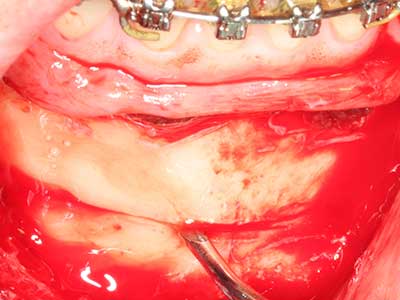

En la extracción de bloques óseos la piezocirugía también presenta ventajas adicionales: Además de la alta precisión en la osteotomía que ya se ha descrito antes, se ha comprobado que el uso de los delgados insertos de sierra resulta especialmente cuidadosas con el hueso. Frente a esto, sobre todo cuando se usan las fresas de Lindemann, cabe esperar pérdidas en la extracción significativamente más altas debido al mayor grosor de la parte frontal del cabezal (Lakshmiganthan, Gokulanathan et al. 2012). La separación basal que se necesita en particular en los injertos de bloque extraídos de forma retromolar se ve facilitada mediante sierras perpendiculares especialmente previstas a tal fin, lo que permite considerar que la cirugía piezoeléctrica es un procedimiento preciso y seguro para la obtención de bloques de hueso en el área retromolar (Happe 2007) (fig. 1-12).

Aplicación: Partición ósea / Cortical Split